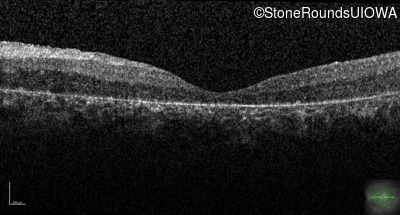

Optical Coherence Tomography - Right - 20/200 +1

Exemplar / OCT Stack